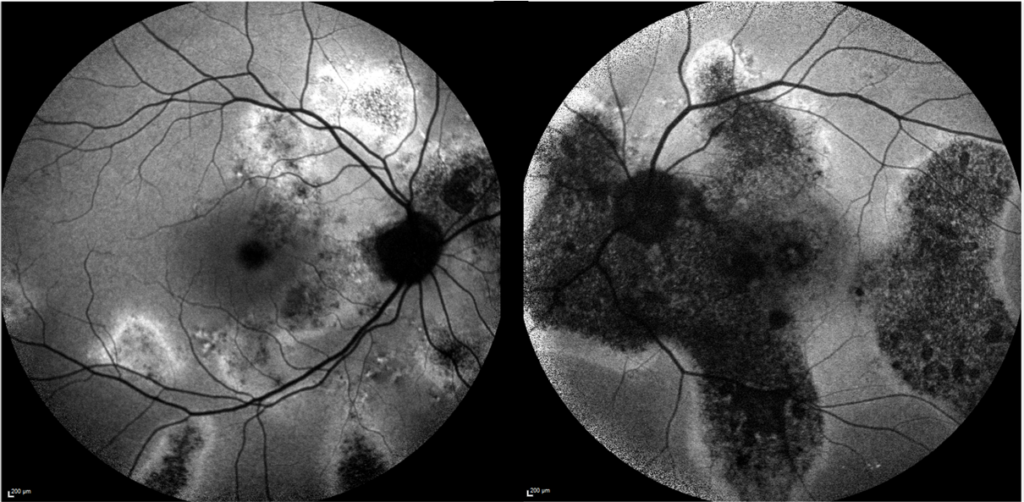

Rétinophotos couleurs du pôle postérieur chez un patient qui présente des altérations de l’épithélium pigmentaire multiples

Rétinophotos en autofluorescence des deux yeux montrant plusieurs coulées gravitationnelles